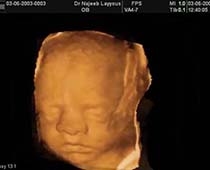

- Fetal Face Ultrasound Photos

- 3D Fetal Profile Ultrasound Scan Photos